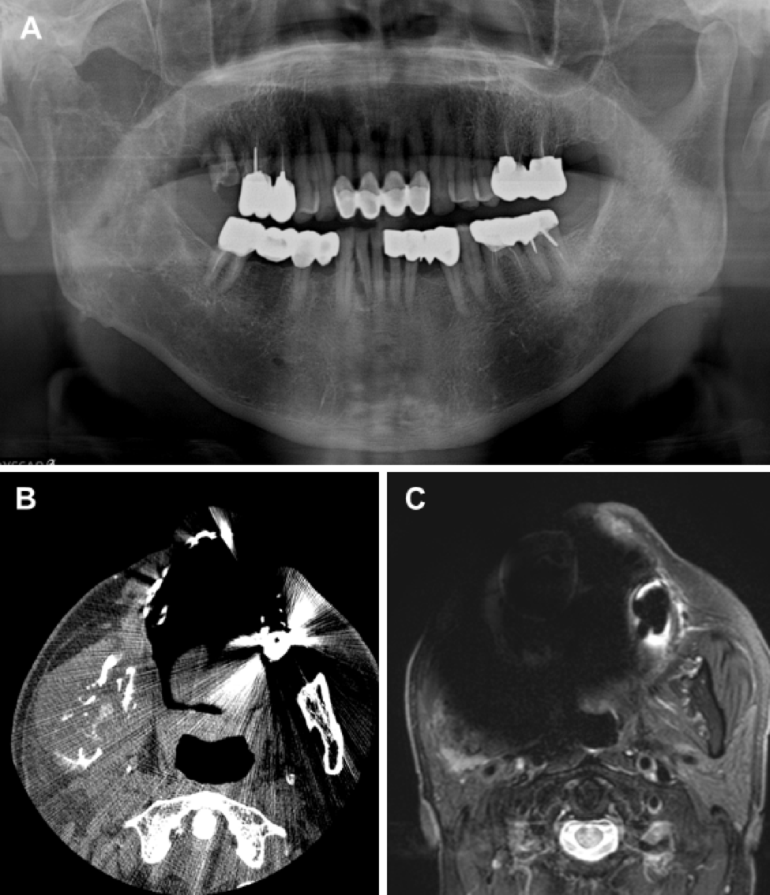

A patient with lymphoma involving the right mandibular ramus. (A) Panoramic radiograph. (B) Axial CT image demonstrating a soft tissue mass with mandibular bone destruction. (C) Axial MR image. The lesion is obscured by severe metal artifacts, making diagnosis impossible.